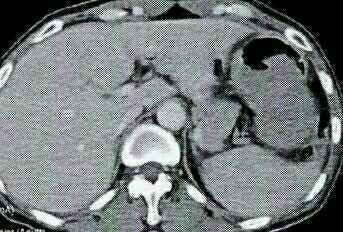

胃镜提示胃底部和胃窦部有小片状糜烂。腹部CT结果提示:近胃角部胃浆膜面肿块,首先考虑胃肠道间质廇。血常规,生化等未见明显异常。

胃镜提示胃底部和胃窦部有小片状糜烂。腹部CT结果提示:近胃角部胃浆膜面肿块,首先考虑胃肠道间质廇。血常规,生化等未见明显异常。治疗:评估手术指征和能否耐受手术, 向病人及其家属交代病情, 签署手术同意书,手术室内采用气管插管全身麻醉,常规消毒铺巾,通过手术切除肿瘤治疗。后把切除组织送病理,经病理确诊为良性。术后给予抗感染等对症治疗,病人康复出院,经半年的随访未有见复发。